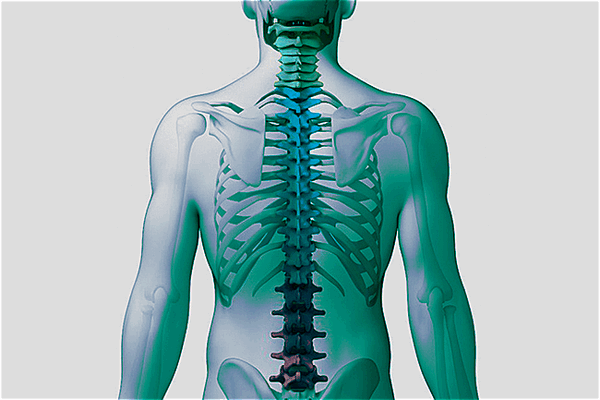

Что показывает КТ позвоночника?

Компьютерная томография позвоночника — это современный метод послойного сканирования сегментов позвоночного столба с последующей реконструкцией изображения в трех проекциях. Техника проведения процедуры основана на рентгеновском излучении, а именно, на принципе, что различные по плотности и морфологии ткани на сканах визуализируются по-разному.

На томограммах в трех проекциях можно рассмотреть позвонки, увидеть, не повреждены ли отростки, нет ли компрессии (сдавления позвоночного канала).

Рентгеновские лучи обладают высокой разрешающей способностью, а данные КТ записываются и обрабатываются на компьютере в высоком качестве. Это делает компьютерную томографию прецизионным и наиболее предпочтительным методом оценки костей и суставов после травм или перед операциями позвоночнике. Стандартная рентгенография — это плоскостное двухмерное изображение, уступающее данным сканирования на современном мультиспиральном томографе. КТ будет наиболее информативна в случае с диагностикой инфекционно-воспалительных процессов (остеомиелита), опухолей и костно-деструктивных процессов.

Компьютерная томография шейного, грудного, пояснично-крестцового отдела позвоночника позволяет в высоком качестве визуализировать не только кости и суставы. Методика отлично зарекомендовала себя в диагностике неврологических нарушений, связанных с посттравматическими изменениями. Обычно это происходит после травмы позвоночника, а иногда даже после неловкого движения. Если боль становится хронической и снижает качество жизни пациента, лечащий невролог может рекомендовать сделать КТ позвоночника для уточнения причины. По локализации болевых ощущений лечащий врач определит, томография какого отдела позвоночника необходима в данном случае.

При онемении рук и головных болях рекомендуют делать КТ шейного отдела позвоночника. При проблемах с ногами и дисфункции органов малого таза — КТ пояснично-крестцового отдела позвоночника. КТ грудного отдела позвоночника позволяет оценить не только состояние позвонков в этом сегменте. На томограммах грудного отдела позвоночника врач-рентгенолог также увидит переломы ребер, инородные предметы в легких, новообразования плевры, средостения, дыхательных органов.

КТ позвоночника показывает:

- Текстуру, строение, плотность костной ткани. Любые повреждения, опухоли и патологические изменения (в том числе остеохондроз позвоночника, метастазы);

- Позвоночный канал и межпозвонковые отверстия;

- Отростки позвонков;

- Спинной мозг.